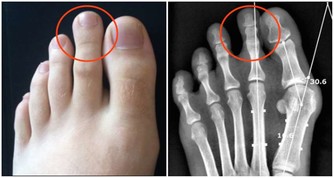

引起手麻較為常見原因的有以下幾種: 上肢神經卡壓:

一是拇、食、中指的麻木疼痛,

常有夜間麻醒史,醒後活動可好轉。

嚴重者可伴有手部肌肉萎 縮,影響手的精細動作,

這是因為正中神經在腕部受到壓迫,

即所謂的「腕管綜合徵」;

二是環、小指的麻木疼痛,也可有夜間麻醒史,

嚴重者伴有肌萎縮,環、小 指的屈指力下降,

影響精細動作。這是因為神經在肘部受到卡壓,

即所謂的「肘管綜合徵」。